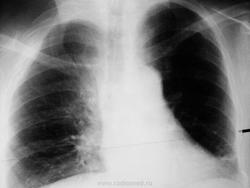

Просто показать.Случается и верхние рёбра ломаются. Женщина. ДТП (падение с велосипеда)

Механизма травмы не помнит (Бахус виноват), привезли с улицы. I ребро, действительно целое. Сломаны II-IV р.

Красивый снимок. Второй раз, что ли, уже упала ) ? Слева тоже старые переломы. Надо в рекомендациях посоветовать транпортное средство поменять )